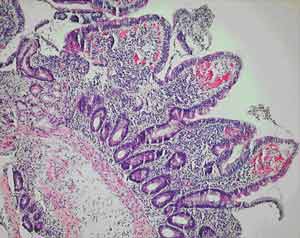

All of our patients were Indigenous patients living in remote Indigenous communities. The alcohol use by the first patient clouds the picture, as high alcohol intake is associated with nutritional deficiencies. However, the partial villous atrophy on biopsy is more suggestive of tropical sprue. Additionally, despite being in hospital and not drinking alcohol for 2 weeks, there was no response in his weight or biochemical test results until therapy for tropical sprue commenced. Finally, his weight gain and improvement in biochemical test parameters continued despite ongoing alcohol misuse on discharge.

A number of studies of chronic diarrhoea in Indigenous Australian children have documented partial villous atrophy on small bowel biopsy.6,7 Higher colony counts and more frequent isolation of gram-negative organisms are found in duodenal aspirates from Indigenous children with chronic diarrhoea.8 Some of these studies noted a similarity with contemporary Indian studies of tropical sprue, but therapy with antibiotics and folate does not seem to have been considered in the Indigenous children.

Our anatomical pathology service believes that small-bowel biopsies from Indigenous patients from remote communities do show a subtle increase in inflammatory cells (Dr M Jagusch, Anatomical Pathology Department, Cairns Base Hospital, personal communication), perhaps representing the subclinical tropical enteropathy described above. The relatively high incidence of gastrointestinal infections in these Indigenous communities may explain these histological findings and, by initiating the pathological process, may predispose these populations to tropical sprue.